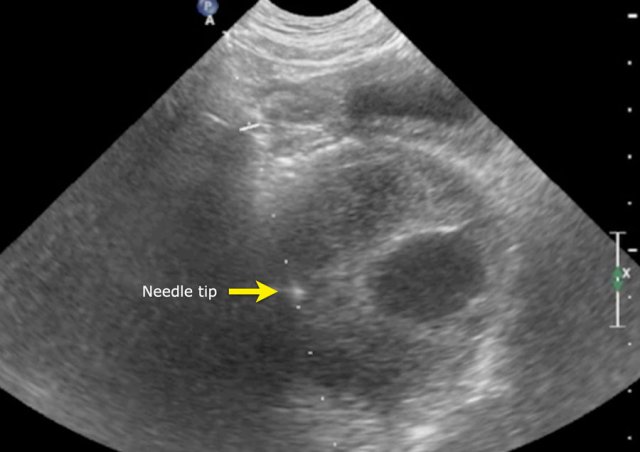

Images

The MRI is of a nine-months-old girl with a tumor in the left abdomen. The MRI shows a tumor of the left adrenal gland, partially solid, partially cystic. Multiple liver metastases are present.

The tumor was biopsied. There was constant blood loss through the guiding needle. At the end of the procedure two gelatin foam plugs were placed (echogenic stripes (arrows).